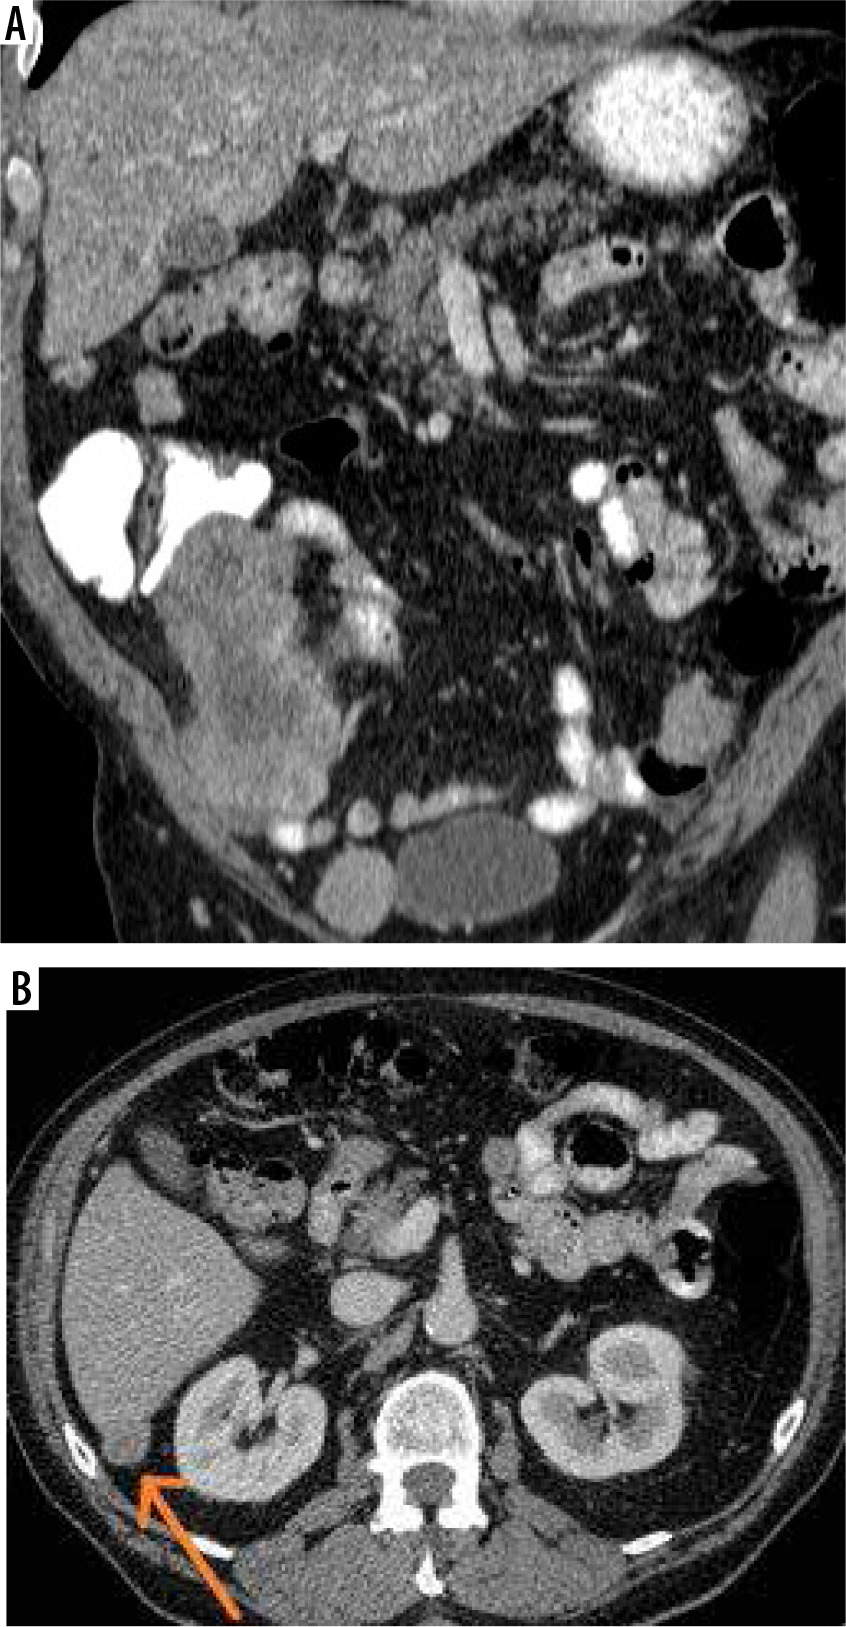

Figure 2

Female, 78-year-old. Endometrial cancer. A) Computed tomography (CT) – nodular implants in the abdominal peritoneum. B) CT – nodular implants in the greater omentum

Figure 5

Male, 74-year-old. GIST. A) Computed tomography (CT) – metastatic involvement of the peritoneum. B) CT – subcapsular implant on the liver surface